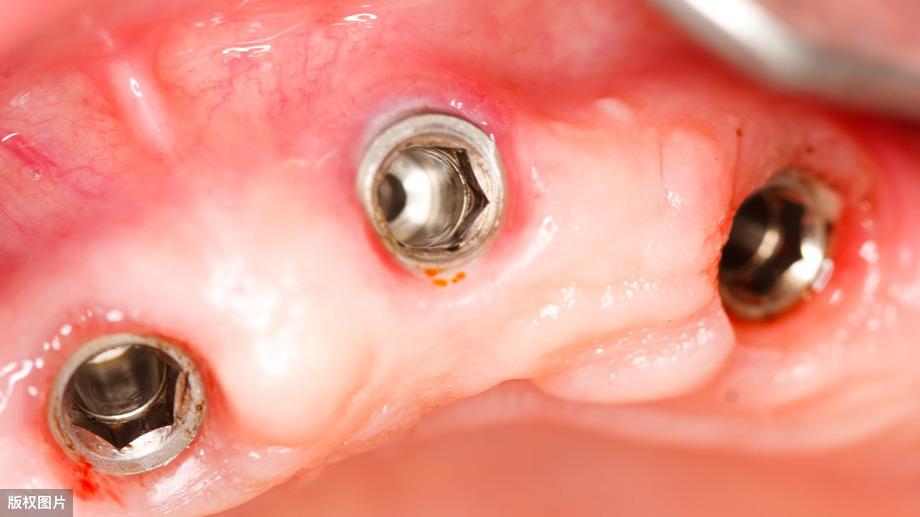

種牙后X光片,未戴冠。

種牙前X光片